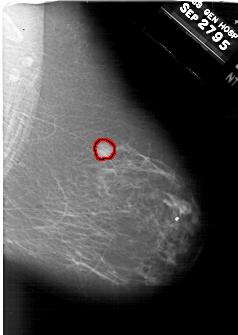

A_1895_1.LEFT_MLO

LEFT_MLO LINES 6346 PIXELS_PER_LINE 4411 BITS_PER_PIXEL 12 RESOLUTION 43.5 NON_OVERLAY

FILE: A_1895_1.RIGHT_MLO.OVERLAY

TOTAL_ABNORMALITIES 1

ABNORMALITY 1

LESION_TYPE MASS SHAPE IRREGULAR MARGINS ILL_DEFINED

ASSESSMENT 5

SUBTLETY 5

PATHOLOGY MALIGNANT

TOTAL_OUTLINES 1

BOUNDARY